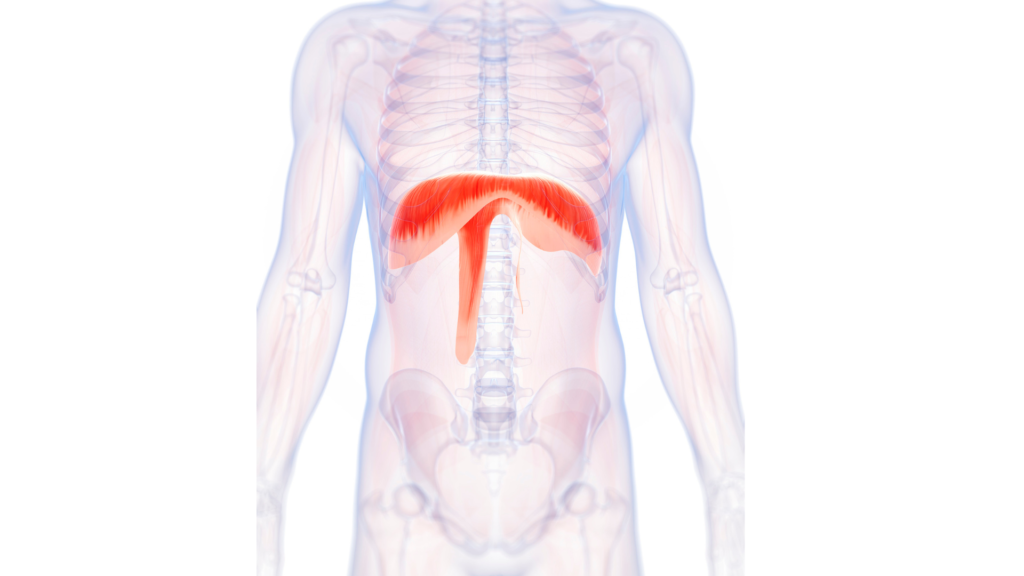

横隔膜は「呼吸筋」であり「姿勢筋」でもある

横隔膜は単なる呼吸筋ではありません。

体幹安定に重要なインナーユニット(横隔膜・腹横筋・骨盤底筋・多裂筋)の一部です。

吸気時に横隔膜が下降し腹腔内圧が高まることで、脊柱は安定します。

しかしストレスや猫背姿勢により横隔膜の可動が制限されると、腹腔内圧(IAP)が適切に作れません。

慢性腰痛患者では横隔膜の位置異常や筋厚変化が報告されています。つまり横隔膜の機能低下は“硬さ”だけでなく“痛み”にも関与します。

体が硬い人は、横隔膜が動いていない可能性が高いです。